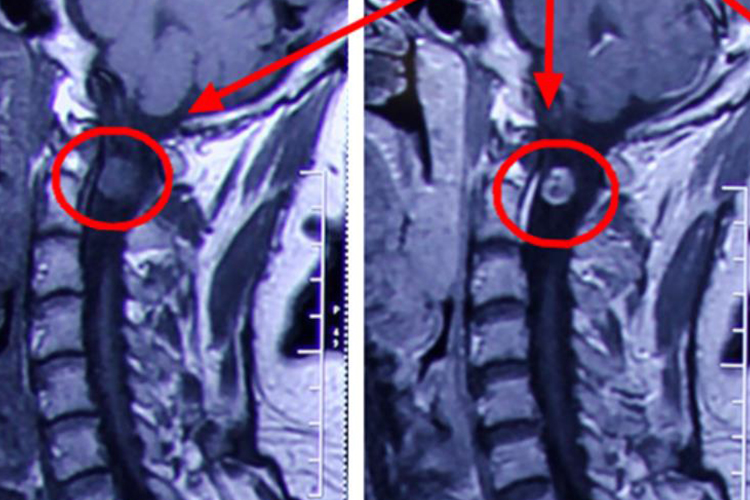

良性神经鞘瘤多经影像学检查明确诊断,肿瘤体积一般不大,直径为1-4cm,形体长圆、光滑、界限清楚,顺神经干走行,移动性小,与神经干垂直方向移动度大。瘤体较小者呈实质性,瘤体大者因其有囊变、出血或变性,可呈囊肿状。